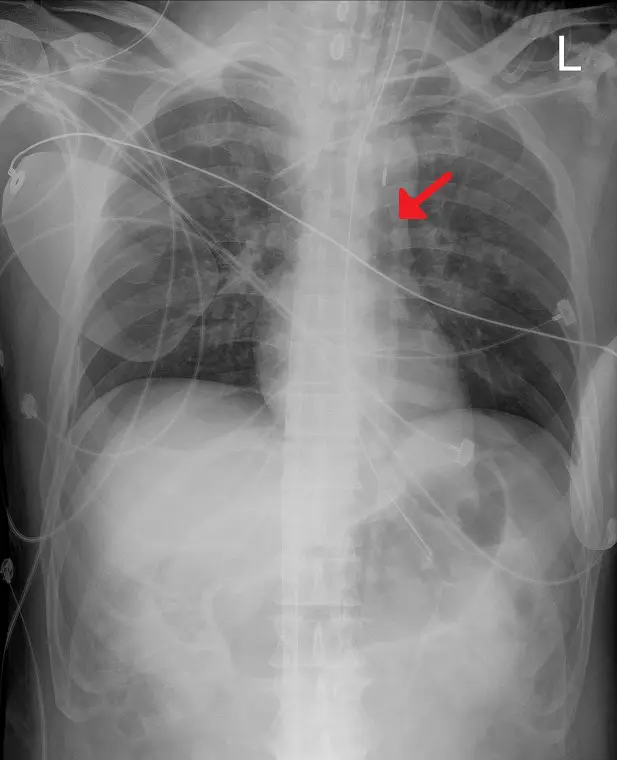

下圖是一位加護病房中狀況穩定的心臟疾病患者之 X 光影像,下列敘述何項正確?

A紅色箭號所指裝置是左心室輔助器( LVAD )

D紅色箭號所指裝置可以增加心肌灌流

- X 光影像顯示胸腔縱膈腔區域有一條不透光導管 (Radiopaque catheter),其尖端/標記位於降主動脈 (Descending Aorta) 區域,約在氣管隆突 (Carina) 水平或稍下方(理想位置為左鎖骨下動脈開口遠端約 2 公分處)。

- 紅色箭頭所指之處即為 IABP 導管的遠端不透光標記 (Radiopaque tip marker)。

- 影像中並未見到左心室輔助器 (LVAD) 特有的大型幫浦機殼 (Pump housing) 或位於心尖處的流入管路。

- 解剖位置:導管走行於脊柱左側的降主動脈路徑上,符合 IABP 由股動脈 (Femoral artery) 逆行置入的路徑特徵。